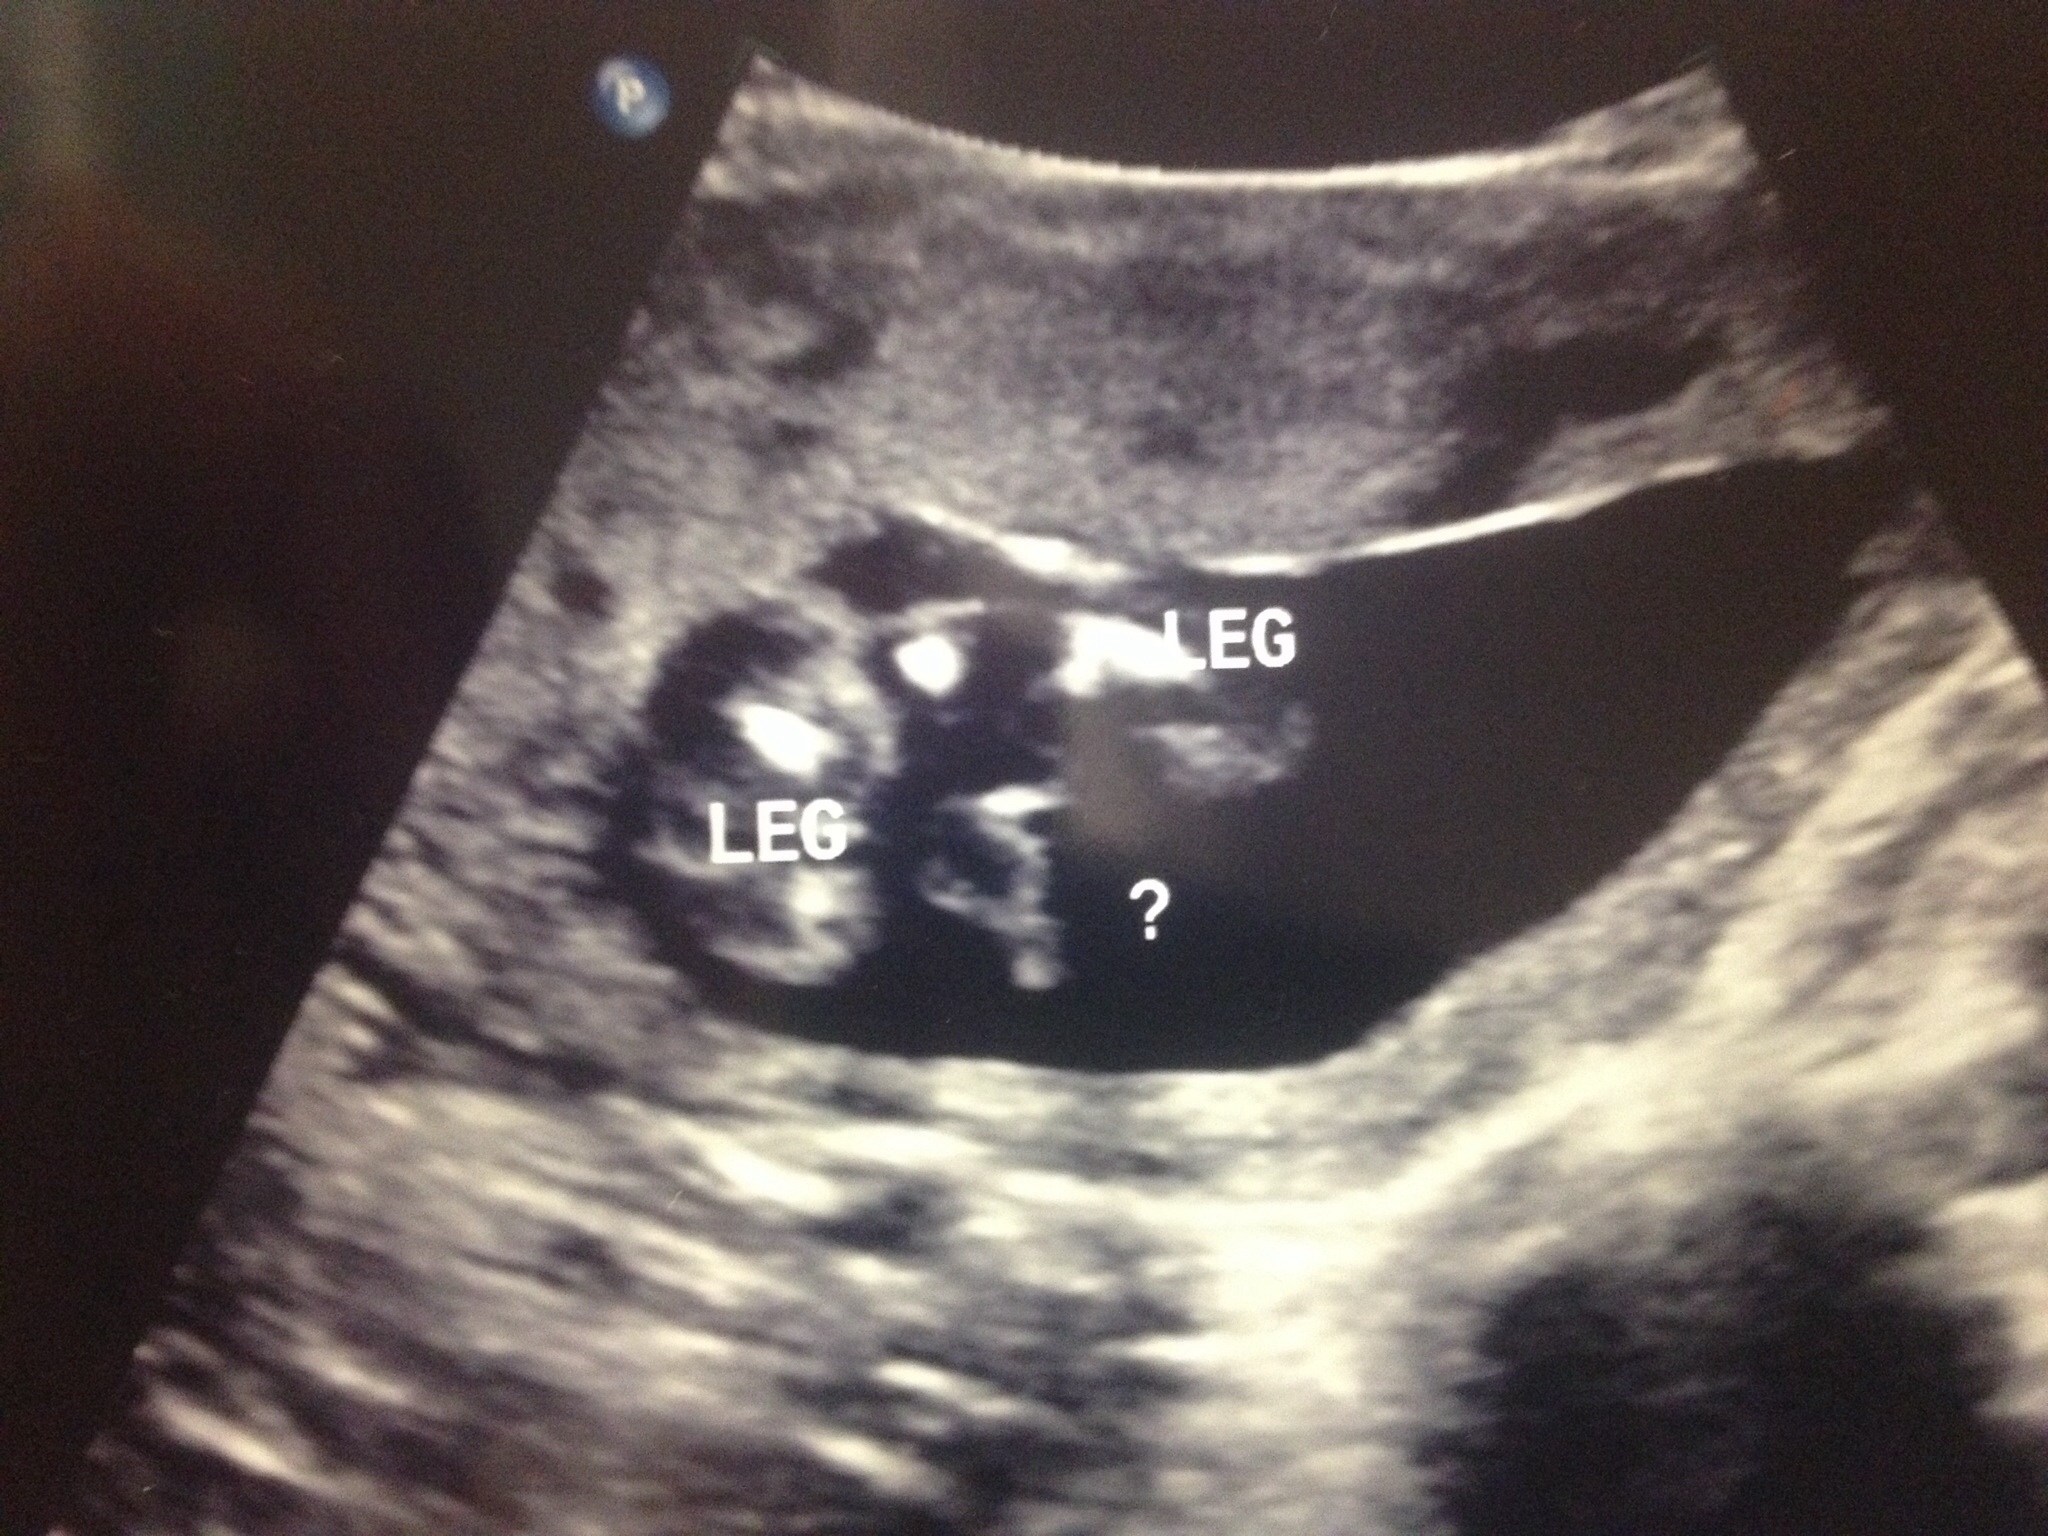

Just had our anatomy scan this morning. .. It's a boy! The tech only said she was 98% since his legs were a bit closed... I'm thinking 98% is still a sure thing?

I had my anatomy scan this morning... All looked great and healthy baby.... The kicker: about 1 month we had a fun little ultrasound at my work by one of the doctors who was "75% sure it was a girl" Baby kept it's legs crossed almost the entire time but opened long enough to give us a shot of HIS manhood..... Totally SHOCKED!!!!!

The kicker: about 1 month we had a fun little ultrasound at my work by one of the doctors who was "75% sure it was a girl"

Baby kept it's legs crossed almost the entire time but opened long enough to give us a shot of HIS manhood.....

Totally SHOCKED!!!!!